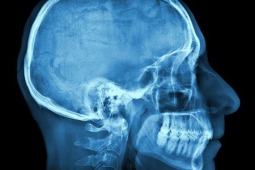

Urazy, których doświadczają sportowcy mogą prowadzić do trwały zmian w ośrodkowym układzie nerwowym i w efekcie do zaburzeń pamięci. Takie wnioski na łamach JAMA Neurology prezentują naukowcy z University of Texas w Dallas. Badanie zostało przeprowadzone na 28 emerytowanych zawodnikach National Football League.

Celem pracy było sprawdzenie, czy powtarzane wstrząśnienia mózgu mają wpływ na jego funkcjonowanie w późniejszym czasie. Jest to jeden z najczęstszych urazów - szacuje się, że w USA każdego roku dochodzi do 1,5-3,8 milinów wstrząśnień mózgu związanych z uprawianiem sportu. Uczestnicy prezentowanego badania byli w wieku 36-79 lat – średnio 58,1 lat dla graczy NHL (n=28) oraz 59 lat w grupie kontrolnej (n=27). W sumie w pracach analizowano wyniki 28 graczy NFL - w tym 8 z łagodnymi zaburzeniami poznawczymi (mild cognitive impairment, MCI) i historią wstrząśnienia mózgu oraz 21 zdrowych uczestników z grupy kontrolnej i dodatkowych 6 osób kontrolnych z zaburzeniami poznawczymi bez wstrząśnień mózgu w wywiadach. Spośród sportowców, 17 osób zgłaszało doświadczenie wstrząśnienia mózgu 3 stopnia z utratą przytomności, a 8 miało wcześniej łagodniejsze wstrząśnienie mózgu i było zdiagnozowanych z łagodnymi zaburzeniami poznawczymi. U wszystkich uczestników wykonywano badania obrazowe głowy oraz testy oceniające pamięć.

Okazało się, że osoby ze wstrząśnieniami mózgu w historii niediagnozowane z łagodnymi zaburzeniami poznawczymi gorzej wypadały w testach pamięci słownej niż osoby z grupy kontrolnej, chociaż ich wyniki mieściły się w granicach normy. Natomiast osoby ze wstrząśnieniami w wywiadach oraz MCI osiągały gorsze wyniki w testach niż osoby z obu wcześniej wspomnianych grup. W badaniach obrazowych wykazano natomiast, że objętość hipokampa u emerytowanych graczy NFL z przynajmniej jednym wstrząśnieniem mózgu w stopniu 3 była znacząco niższa niż wśród osób z grupy kontrolnej. Badacze wykryli także, że sportowcy ze wstrząśnieniami mózgu oraz zaburzeniami poznawczymi mieli mniejszą objętość lewego hipokampa niż osoby z grupy kontrolnej z zaburzeniami poznawczymi. Co więcej, okazało się także, że wszyscy uczestnicy (n=7) badania w wieku powyżej 63 lat, którzy doświadczyli wstrząśnień mózgu z utratą przytomności byli zdiagnozowani z łagodnymi zaburzeniami poznawczymi, podczas gdy wśród 5 odpowiadających im graczy, którzy nie doświadczyli urazów OUN z utratą przytomności, tylko jeden miał zdiagnozowane zaburzenia poznawcze.